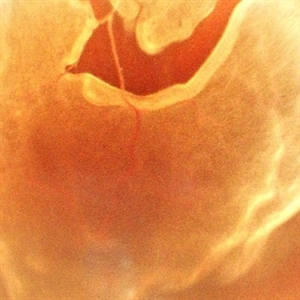

A Vessel That Would Not Let Go

May 5 2025 by Malvika Singh

Fundus photograph of a retinal detachment showing a horse shoe shaped tear and a bridging vessel.

Photographer: Dr Tejaswita Verma, Retina Foundation, Ahmedabad, India

Imaging device: Mirante SLO/OCT

Condition/keywords: bridging vessel, horseshoe tear